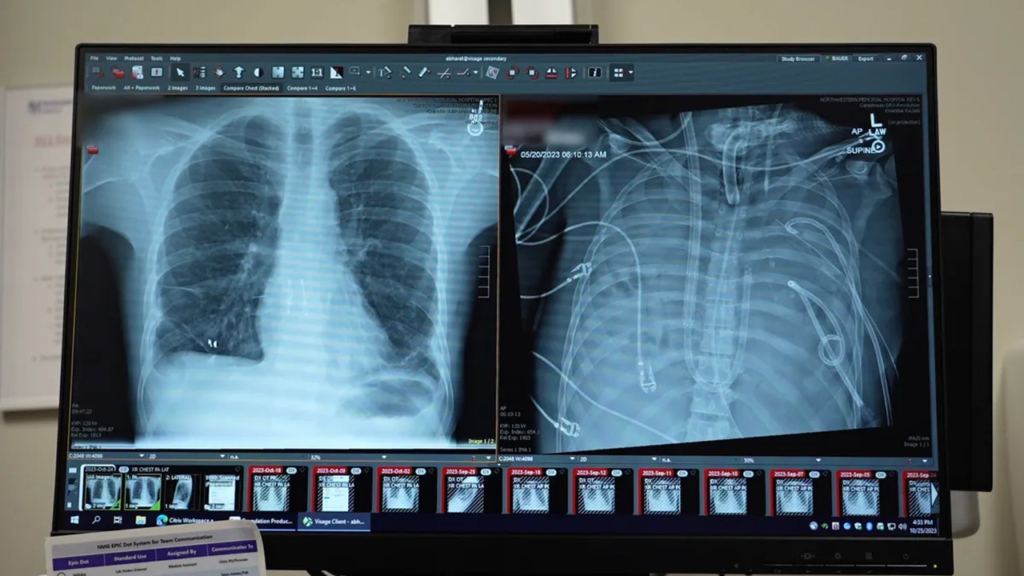

Her şey sağlıklı bir erkeğin Influenza B virüsüne yakalanmasıyla başladı. Başlangıçta basit bir grip gibi görünen durum, kısa sürede akut solunum yetmezliğine dönüştü ve hastaneye ulaştığında durumu artık kritik bir noktaya gelmişti. Antibiyotikler ve geleneksel oksijen tedavileri, akciğerlerdeki yıkımı durdurmaya yetmedi. Hastanın akciğerleri o kadar ağır hasar almıştı ki, hem kalbi hem de böbrekleri iflas etmeye başladı. Operasyonu yöneten Profesör Ankit Bharat, hastanın hastaneye ulaştığı an kalbinin durduğunu ve akciğer dokusunun geri dönülemez şekilde bozulduğunu belirtiyor. Bu aşamada klasik yöntemler yetersiz kalınca, tıp ekibi radikal bir karara imza atarak, iltihap odağı haline gelen akciğerleri tamamen çıkarmayı ve hastayı yapay bir düzenekle hayatta tutmayı denedi.

Akciğerlerin vücuttan çıkarılması, enfeksiyonun kontrol altına alınması için tek yol haline gelmişti ancak bu durum devasa bir teknik sorunu da beraberinde getirdi. Kalp ve akciğerler birbirine kopmaz bağlarla bağlı olduğu için, akciğerler olmadan kanın oksijenlenmesini sağlamak ve kalbin zayıflamış ritmini korumak neredeyse imkansız bir görevdi. Uzmanlar, kanı vücut dışında oksijenlendiren mevcut teknolojileri daha da geliştirerek, kalbin üzerindeki basıncı dengeleyen özel bir sistem kurdu. Bu yapay düzenek, iki gün boyunca hastanın kanındaki karbondioksiti temizleyip oksijen sağlayarak diğer organların iyileşmesine zaman tanıdı.

Nakil için uygun organlar bulunduğunda, cerrahlar hastanın genel durumunun nakil işlemini kaldırabilecek kadar düzeldiğine karar vererek operasyonu gerçekleştirdi. Çıkarılan eski akciğerler üzerinde yapılan incelemeler ise kararın ne kadar yerinde olduğunu bir kez daha kanıtladı; zira o dokuların iyileşme şansı tamamen ortadan kalkmıştı. Nakilden bu yana geçen iki yıllık süreçte hastanın tamamen sağlığına kavuşması ve normal hayatına dönmesi, bu yöntemin başarısını tescilledi. Profesör Bharat, özellikle genç yaştaki hastaların ağır akciğer hasarı nedeniyle kaybedilmesinin önüne geçebilecek bu yöntemin, gelecekte daha fazla hastanede uygulanabileceğini ve bağışçı bekleyen hastalar için hayati bir zaman kazandıracağını umut ediyor.